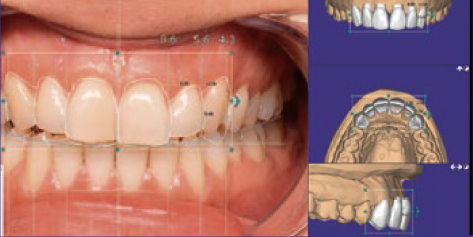

写真データをCAD上にインポート

補綴物描画

咬合器動作の再現